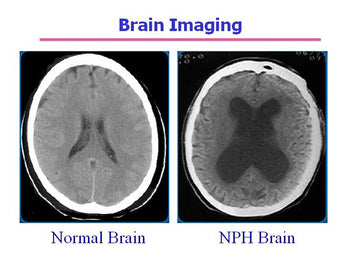

NPH (Normal Pressure Hydrocephalus) is a condition in which excess cerebrospinal fluid (CSF) accumulates in the brain’s ventricles, causing them to enlarge, while the pressure within the ventricles remains normal. This condition can result in a triad of symptoms, often affecting elderly people.